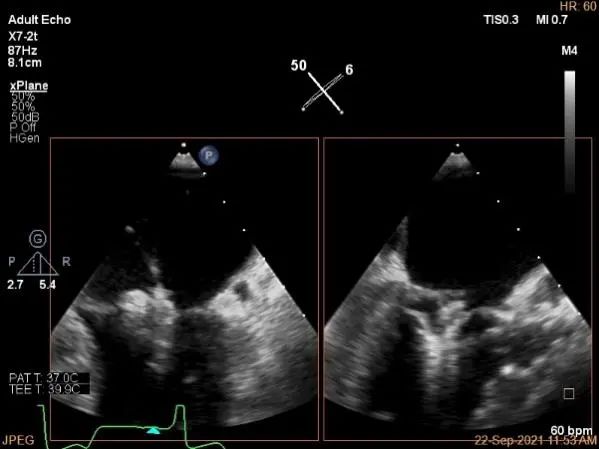

术中超声

P2区脱垂,宽14.8mm,Gap:3.3mm

3D-color,返流重度,3+级

麻醉状态下左肺静脉血流频谱

MVA:6.67cm²

房间隔穿刺点选择

穿刺高度:4.3cm